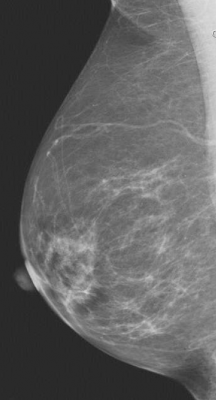

"In general, we refer to breast density as being determined by mammographic appearance, and that has, by and large, in the past been done by visual estimation by the radiologist — in other words, subjective and qualitative," said Perry. "The automated system we used in the study is an algorithm that can be automatically and easily applied to a digital mammogram, which allows an objective and, therefore, quantitative density measurement that is reproducible."

Breast cancer patients showed higher mammographic density than healthy participants up to the age of 50. The healthy controls demonstrated a significant decline in density with age following a linear pattern, while there was considerably more variability in density regression among the breast cancer patients.